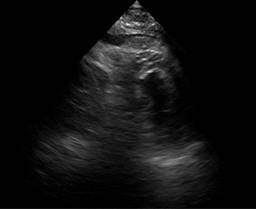

A transthoracic echocardiogram was performed that showed septoapical, apical, inferior apical akinesia, no thinned cardiac segments. Left ventricular ejection fraction (LVEF) 45%, type 1 diastolic dysfunction E/A 0.6, E/e 10, normal dimensions of the right heart chambers with normal right ventricular ejection fraction at rest. Systolic pulmonary artery pressure 26 mmHg, estimated by tricuspid reverse gradient. No pericardial effusion at rest (Figures 1 to 3). The patient evolved to be hemodynamically stable, so a stress echocardiogram was performed to search for viability/residual ischemia on the 6th day after admission to hospitalization. A 5-stage protocol was initiated, starting at 5 μg/kg/min, reaching 20 μg/kg/min. The patient persisted with septoapical and apical akinesia and developed an ischemic response due to developing basal and medial inferior hypokinesia. No changes were recorded in the electrocardiogram at this dose of dobutamine. Esmolol 30 mg intravenous single dose was administered at the beginning of the recovery phase and the study was terminated. In first minutes of recovery, the patient showed sudden deterioration in alertness and pulseless electrical activity. The echocardiogram showed pericardial effusion with a hematic appearance and echocardiographic data of tamponade (Figures 4 to 6). The patient presented cardiorespiratory arrest, so intravenous fluids were administered and an emergency pericardiocentesis was performed, achieving expansion of the right ventricle but with rapid formation of a new pericardial effusion. Later on, he presented asystole which did not revert to basic or advanced cardiovascular resuscitation.